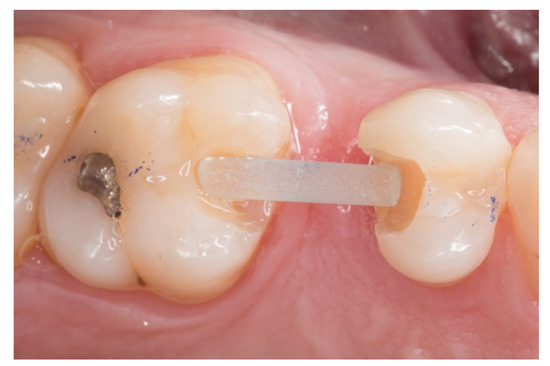

Figure 4.

The horizontal fiberglass pin bonding to the adjacent teeth.

3. The next step consisted of the horizontal fiberglass pin (Rebilda® Post GT, VOCO GmbH, Cuxhaven, Germany) bonding to the adjacent teeth. Firstly, when the isolation of the operative field with the rubber dam was made, the fiberglass pin was adjusted to size and silanization according to the instructions by the manufacturer. Later, the inlay cavities were etched with Ultra-etch® (Ultradent Products Inc, South Jordan, UT, USA) for 20 s, rinsed for 10 s and dried for 10 s. The etched surfaces were covered with a layer of a universal adhesive resin (Prime & Bond® NT, Dentsply Sirona Inc., York, PA, USA), thinned using a brush, and cured for 20 s with a light- polymerizing unit. A flowable resin (Tetric Evo flow®, Ivoclar Vivadent AG, Schaanwald, Liechtenstein) was used to cover the inlay cavities (inlays retainers) and the fiberglass pin to shape the transverse structure of the future bridge (Figure 3 and Figure 4).

4. Afterwards, the pontic core was reinforced with a vertical pin fiberglass structure, which was followed by the same adhesion process mentioned above, obtaining a “T” shape (Figure 5).